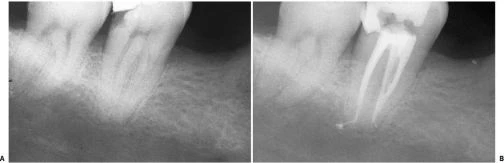

Mở xoang tủy nhìn chung răng cối lớn một hàm dưới có 2 chân phân biệt hình tròn hay thường là elip, ống tủy ở chân xa (hình 11.106) và 2 ống tủy ở chân răng gần. Trong 90% trường hợp chúng đổ ra 2 lỗ chóp khác nhau (hình 11.107) và 10% chúng hợp lại và đổ ra 1 lỗ chóp (hình 11.108).

Hình 11.106. Xoang tủy ở 1 R36: miệng củanhững ống tủy gần khá tròn còn ở ống tủy xa thì thường có hình elip.

Hình 11.107. Các ống gần của răng cối lớn một dưới có những lỗ chóp phân biệt. Chú ý rằng có nhiều ống tủy phụ ở 1/3 chóp (Courtsey of Dr. M. Scianamblo).

Hình 11.108. Các ống gần của răng cối lớn dưới hợp chung lại rồi đổ ra ở cùng một lỗ chóp. Có thể thấy nhiều ống tủy phụ ở chân xa.